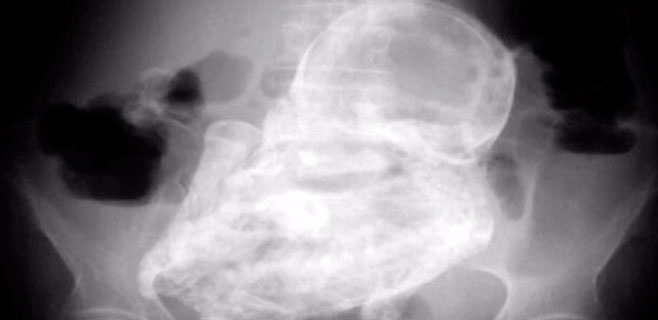

Una mujer colombiana de 83 años ha descubierto, tras acudir a la consulta en un hospital de Bogotá por un dolor abdominal, que tiene un feto calcificado desde hace unos 40 años.

Tras realizarle una radiografía, el examen se estableció que la mujer tenía un feto de 32 semanas de gestación que se calcificó, en un caso de litopedia (un tipo de embarazo extrauterino que no es detectado por la mujer, tras lo cual el feto se calcifica.)